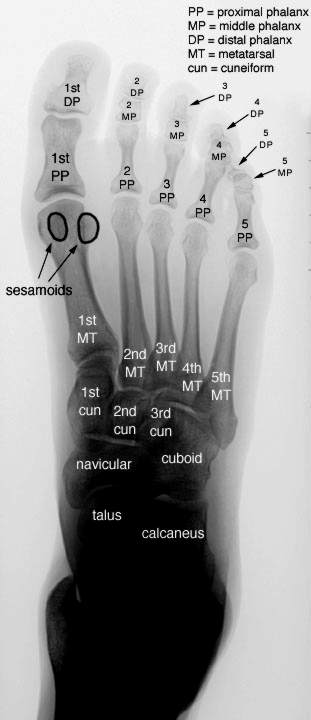

The KRush technique is best utilized in places where nerve density is high, & where deep pressure triggers endorphins (KRush Zones).  For most people, ideal locations are both the feet & hands.  The X-rays here show metacarpals & metatarsals in juxtaposition with phalanx (fingers & toes) arranged so that the 1st, 2nd & 3rd, etc phalanx on the foot X-ray correspond to the thumb, fore, middle & ring finger of the hand X-ray on the right.  On the hand, the 1st, 2nd, etc MT shown in the left X-ray, of course, correspond to carpals.  Other than semantics, hands & feet can be treated equally -- although about +66% of recipients of the technique insist that the KRush zones on the feet generate substantially more "rush". Speaking of "rush", this technique produces a literal flood of neurotransmitters within seconds after being started.  The recipient should be told in advance that they may experience a "rush" and that the entire limb being worked may feel extremely fatigued or "heavy" during the process.  The process is also extremely addictive (in the short term), which means that you should be able to give a recipient some quality time after beginning.  It is my opinion that we could reduce or eliminate much of the pain & anxiety medication prescribed if more people became aware of the KRush Technique.

The soft-tissue in & around the bones is where KRush force should be applied.  It should be very firm but never should hurt the recipient.  Again: Pain receptors should not be triggered during the process if at all possible.  A common technique is to grasp the limb with the hands of the 'KRusher' palms-down on top of the limb w. fingers wrapped around so that the tips apply even pressure between the 1st & 2nd PP, and the 4th & 5th PP (MC when dealing with the hands).  Alternate between 1st & 2nd, 2nd & 3rd; -- And 4th & 5th, & 3rd & 4th -- with respective hands.  Apply deep pressure and HOLD.  Wait 10-15 seconds & release.  Move up or down the limb slightly & repeat.  If connected to monitoring equipment, -- within 30 seconds of beginning: breathing, blood pressure & pulse should begin to drop and vasodilatation in the upper body should increase.  This is often accompanied with a "rush" feeling in the head & the onset of lethargy not unlike opiates cause.